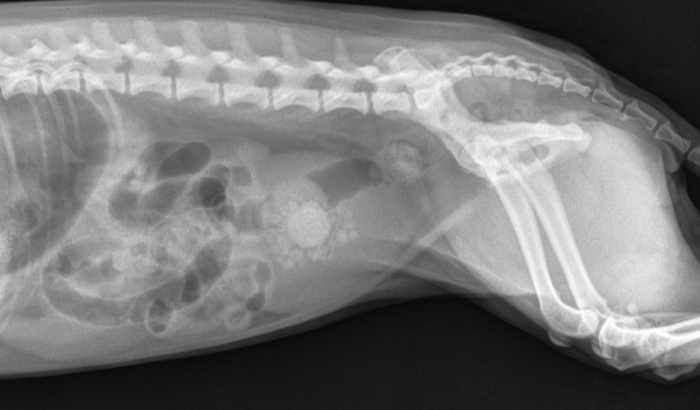

Olá, me chamo Diana, venho pedir a ajuda de vocês, minha cachorrinha estava com pedra na bexiga, foi tratada no começo do ano, seguimos todas as orientações do veterinário, raçao, agua e tudo mais, porem ela voltou a ter um incômodo, quando vimos, ela novamente esta com essas pedras, como foi muito recente, infelizmente ficou apertados para conseguirmos pagar a cirurgia. ela é muito bem tratada, porem é teimosa para beber agua, estamos fazendo o passível para ela nao sofrer mais, conto muito com a ajuda de vocês !!